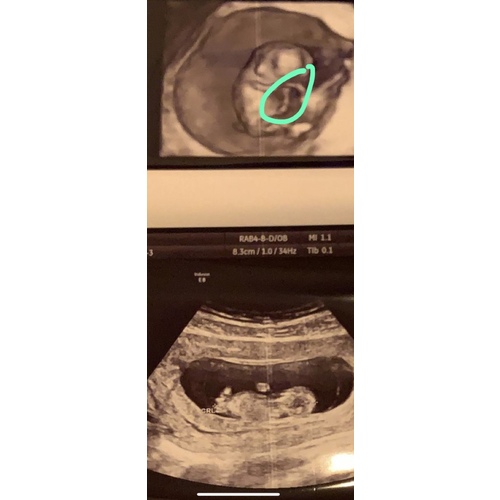

Navelstreng?

Ja denk je dat? Hoort de navelstreng dan daar te zijn?

Lijkt me de navelstreng.

Het is of de Nub of de navelstreng die daar toevallig langs ligt en een stu ...

You made my day. Dank je. Ik was echt zo ongerust. De vroedvrouw zei dat alles ok was hoor maar toen ik thuis kwam en wou genieten dacht ik “oh nee weer iets om te piekeren!”. Wat is dat nub? 😀😅 en de navelstreng is toch wat ik hier op de echo heb aangeduid? Ik ben vandaag trouwens 10+5. Dus gisteren +4. Maar volgens de vroedvrouw was ik gisteren 10+6. Ze zei dat het kan schommelen. De afgelopen 2 sessies klopten toen wel qua weken en dagen. Is dit normaal? 😀

En die nub ligt dan toch eigl normaal tussen de beentjes of kijk ik nu helemaal scheel😅😂